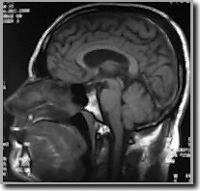

voorbeeld van MRI-beeld

MRI is zonder twijfel een van de betere methode om neurologische aandoeningen op te sporen, denken we hierbij aan scans van de hersenen en het ruggenmerg.